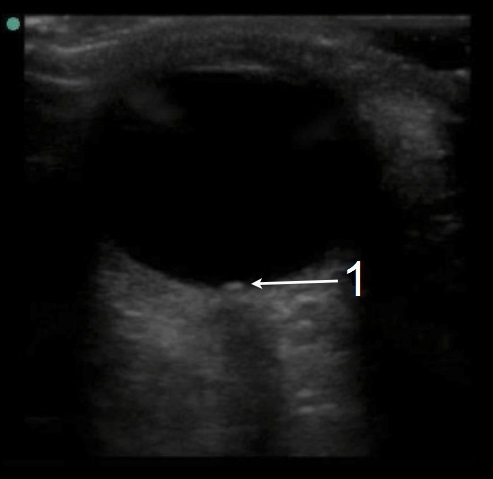

1. Die Schwellung der Papilla nervi optici weist auf eine Stauungspapille hin